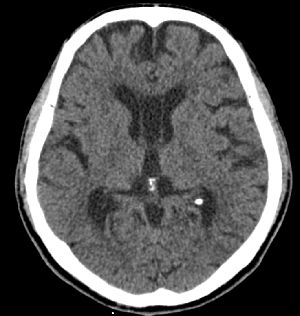

CT는 몸의 단면을 영상화하여 각종 질환을 진단하는 영상의학과 장비 중 하나입니다.

의료용 방사선을 이용하는 X-ray 검사와 비교할 때 인체의 해부학적 구조물이 겹쳐져 보이지 않고 인체의 축상면을 영상으로 획득합니다.

획득된 영상을 전산화된 프로그램을 이용하여 3차원(3D) 영상으로 재구성이 용이하며 인체의 시상면, 관상면 재구성도 가능합니다.

기존 X-ray검사에서는 진단이 불가능했던 질환을 더 자세하게 진단이 가능하게 하는 장비입니다.